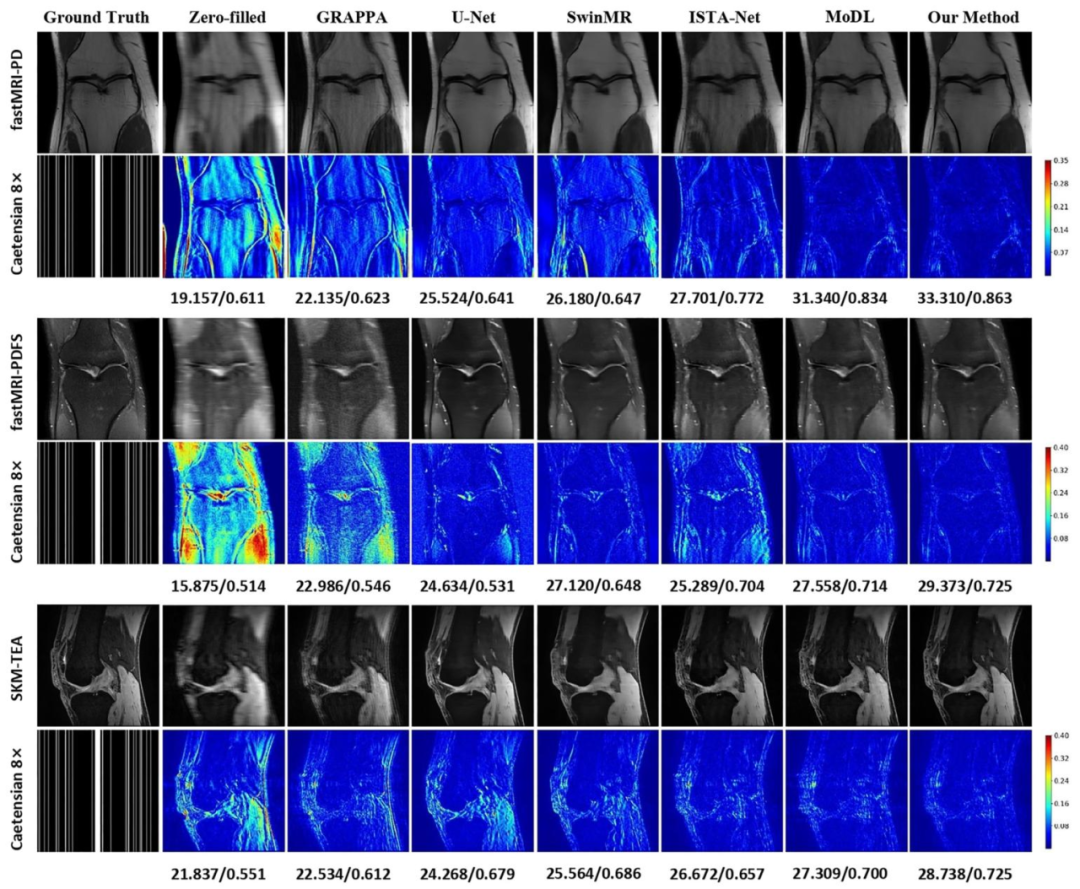

Fig. 6. Comparison of different reconstruction methods using 8× mask on the fastMRI and SKM-TEA datasets. The reconstructed images, magnified details ofpathological regions (marked in the red/yellow boxes), and error maps are presented with the corresponding quantitative metrics in PSNR/LF-PSNR. (Pathology:fastMRI-PD: Cartilage - Partial Thickness loss/defect; fastMRI-PDFS: Bone-Fracture/Contusion/dislocation; SKM-TEA: Effusion)

图6 采用8倍掩码时,不同重建方法在fastMRI与SKM-TEA数据集上的对比 图中展示了各重建方法的重建图像、病理区域的放大细节(以红/黄框标注)及其误差图,并标注了对应的峰值信噪比(PSNR)与病灶导向峰值信噪比(LF-PSNR)定量指标。 (病理类型:fastMRI-PD数据集:软骨部分厚度缺失/缺损;fastMRI-PDFS数据集:骨骨折/骨挫伤/关节脱位;SKM-TEA数据集:关节积液)